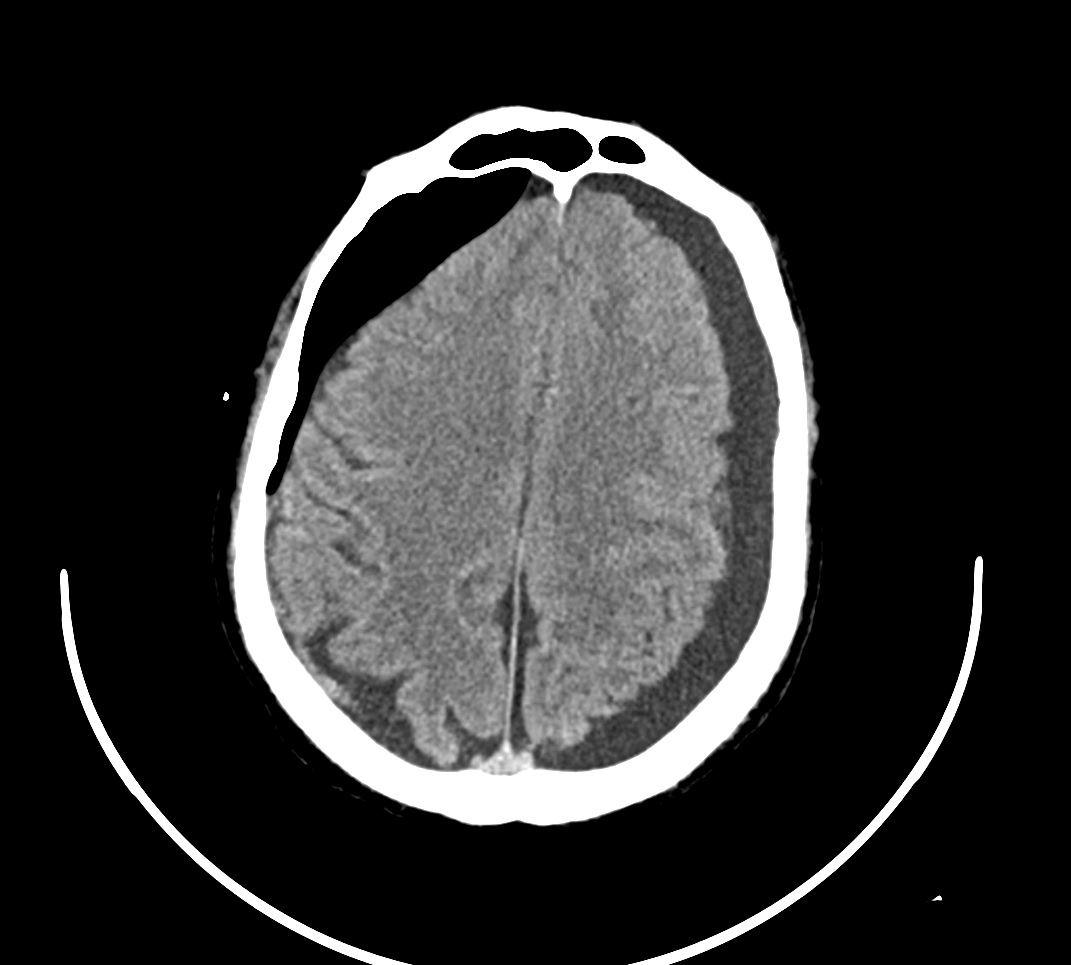

TAC cráneo: Hematoma subdural subagudo-crónico y efecto compresivo con obliteración de surcos frontoparietales.

Último TAC de control: Resolución del HSD derecho.